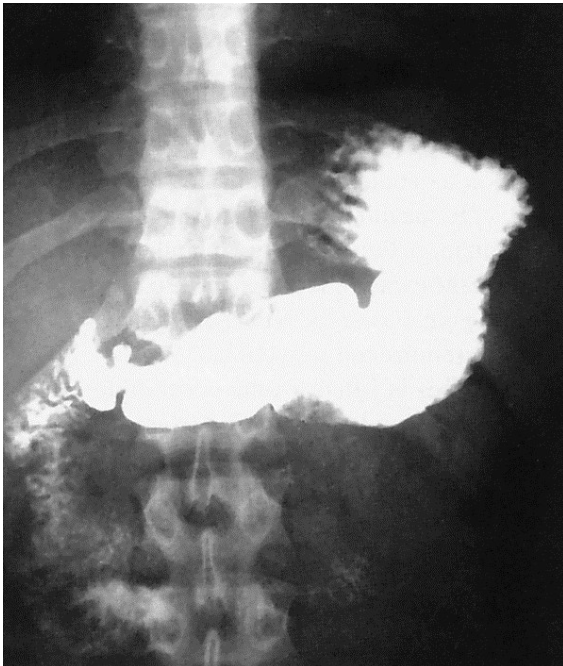

What contrast procedure was performed to produce this image?

Upper Gastrointestinal (UGI) Series

hypersthenic (because stomach is balled up)